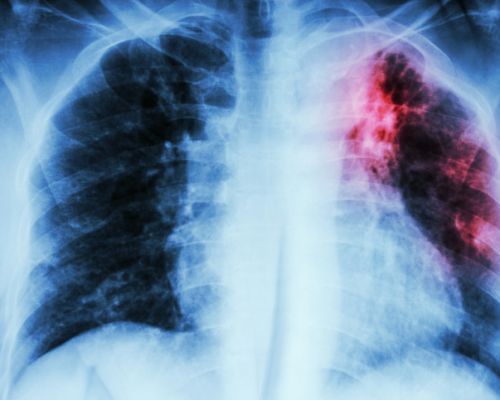

Solovič: cieľ eliminovať tuberkulózu do roku 2030 nie je splniteľný

Pandémia ochorenia COVID-19 nás vrátila takmer o desať rokov dozadu v boji proti tuberkulóze (TBC). Pre TASR to zhodnotil primár oddelenia…